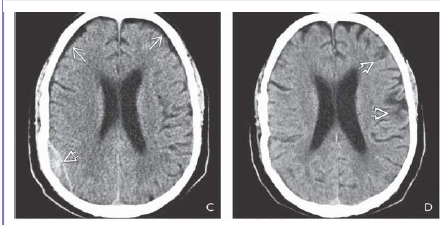

What is shon in B frontal areas 10d after the trauma?

What is shown on the 2nd box?

Repeat NECT scan 10 days later shows that the density of the EDH has decreased significantly.

Small bifrontal hypodense subdural hygromas are now seen. 2-20D. Repeat study 6 weeks after trauma

shows that the EDH has resolved. Foci of left hemisphere encephalomalacia from “contre-coup” injury

are now evident.